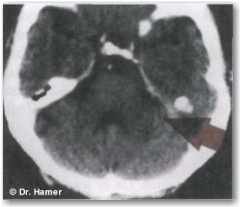

В течение КА-фазы НН всегда проявляется в виде резко очерченных концентрических колец.

На снимке компьютерная томография выявила НН в правом полушарии в моторной коре, что указывает на соответствующий двигательный конфликт («невозможность спастись бегством»), приведший к параличу левой ноги в активной фазе конфликта. У левши такое изображение означало бы конфликт, связанный с партнером.

Биологическое значение такого паралича — «притворная смерть»; в природе хищник зачастую атакует жертву именно тогда, когда та пытается спастись бегством. Другими словами, биологическая реакция жертвы следует логике: «Поскольку я не могу спастись бегством, то притворюсь мертвой», вызывая парализацию вплоть до исчезновения опасности. Людям такая реакция организма свойственна наравне со всеми видами животных.